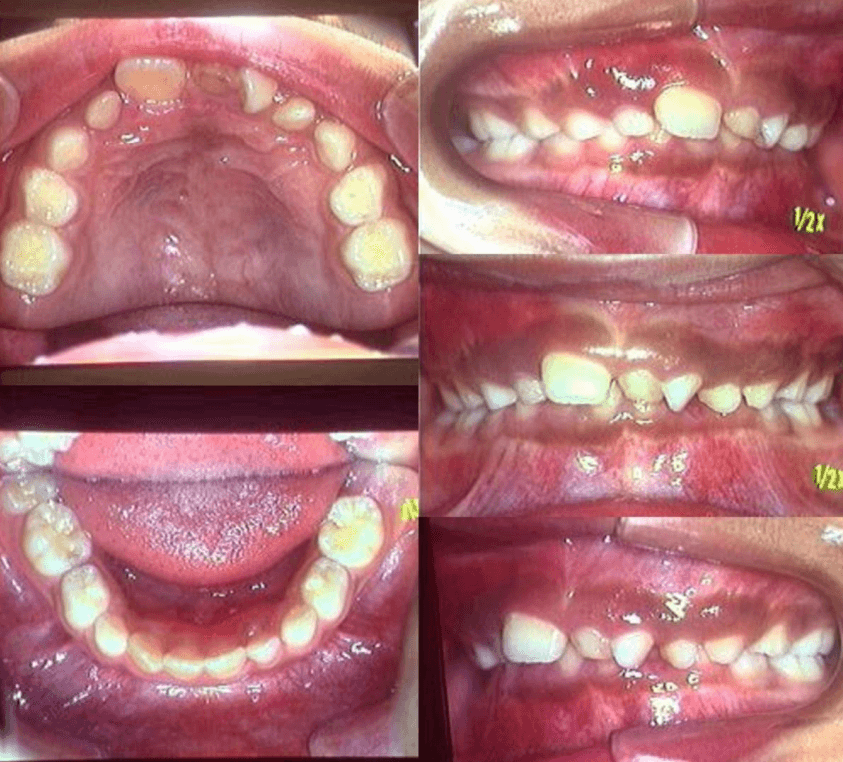

| 年齢・性別 | 7歳1ヶ月の男児 |

|---|---|

| 主訴 | 歯の生えるスペース不足が懸念され、歯列の乱れ(叢生)を整えるために来院された患者様です。 |

| 治療期間・回数 | 1年3ヶ月・11回 |

| 費用 | 420,000円(税別) |